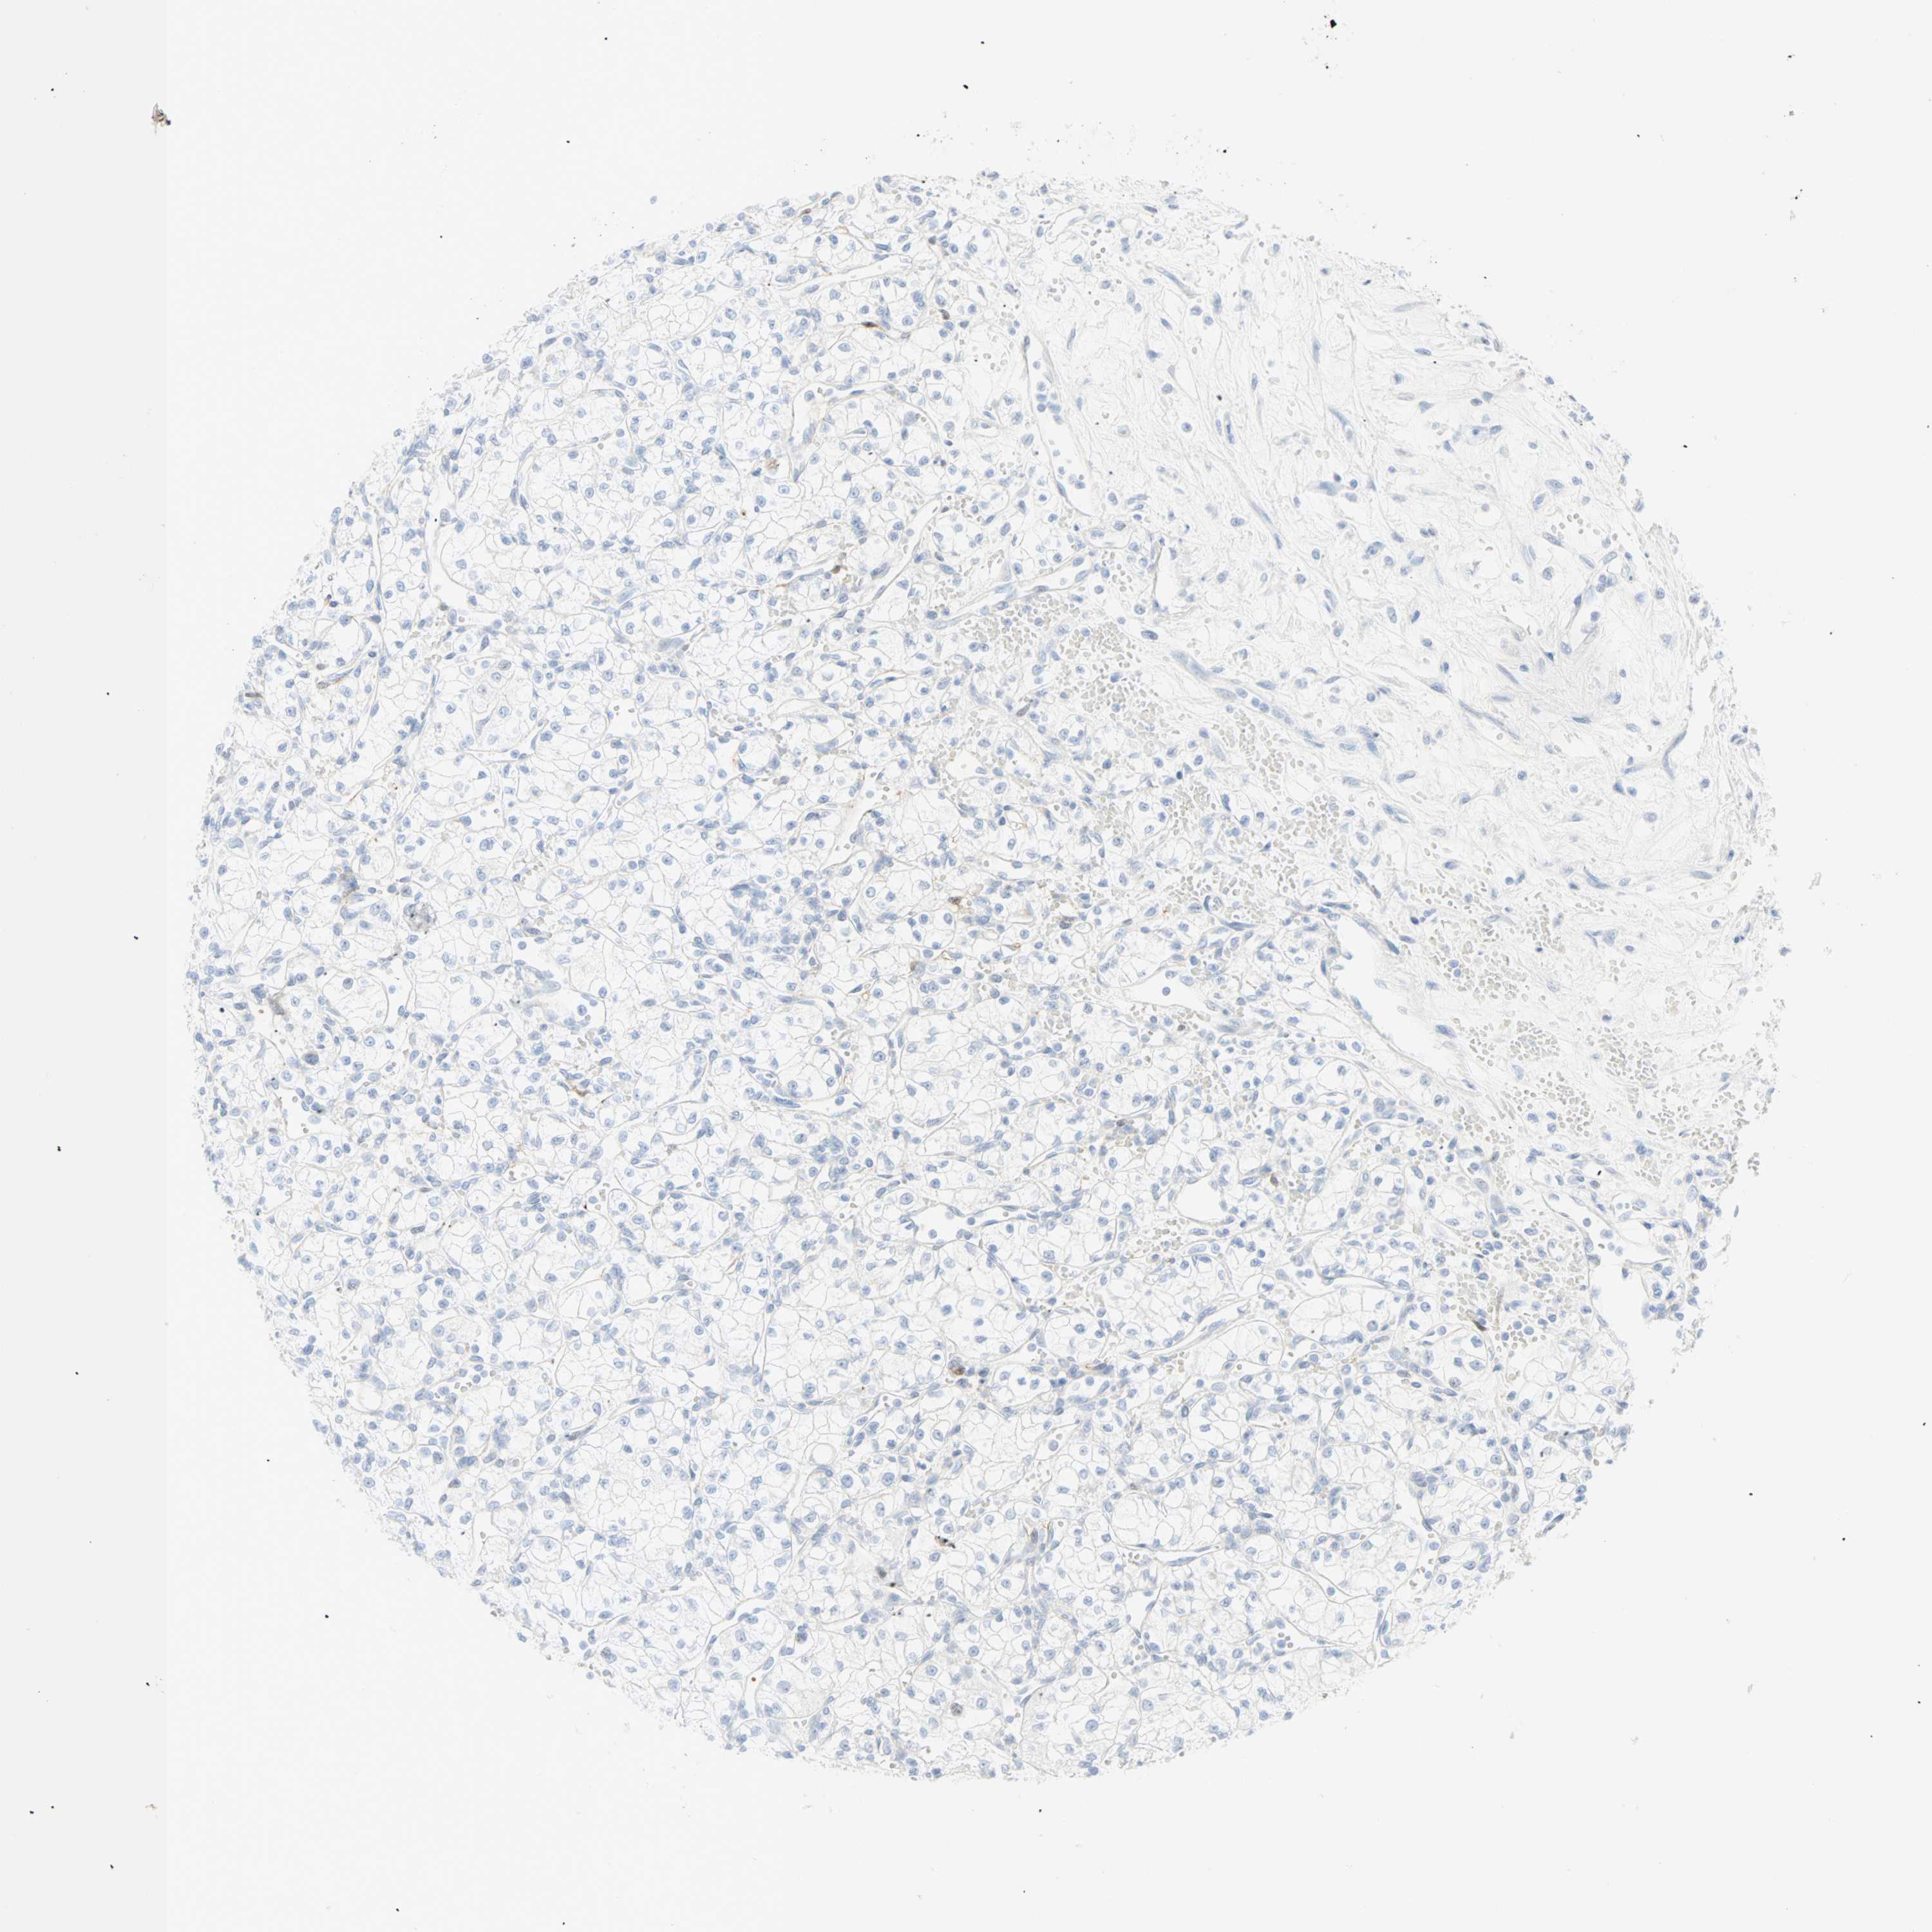

KIDNEY RENAL PAPILLARY CELL CARCINOMA (TCGA) - Interactive survival scatter ploti

The Survival Scatter plot shows the clinical status (i.e. dead or alive) for all individuals in the patient cohort, based on the same data that underlies the corresponding Kaplan-Meier plots. Patients that are alive at last time for follow-up are shown in blue and patients who have died during the study are shown in red.

The x-axis shows the expression levels (FPKM) of the investigated gene in the tumor tissue at the time of diagnosis. The y-axis shows the follow-up time after diagnosis (years). Both axes are complimented with kernel density curves demonstrating the data density over the axes. The top density plot shows the expression levels (FPKM) distribution among dead (red) and alive patients (blue). The right density plot shows the data density of the survived years of dead patients with high and low expression levels respectively, stratified using the cutoff indicated by the vertical dashed line through the Survival Scatter plot. This cutoff is automatically defined based on the FPKM cutoff that minimizes the p-score. The cutoff can be changed by dragging the vertical line or by entering a cutoff value in the square labeled "Current cut-off".

Under the Survival Scatter plot the p-score landscape (black curve; left axis) is shown together with dead median separation (red curve; right axis). Dead median separation is the difference in median mRNA expression between patients who have died with high and low expression, respectively. It is calculated as follows: median FPKM expression of dead patients with high expression - median FPKM expression of dead patients with low expression. This is intended to aid the user in visually exploring custom cutoffs and the associated p-scores and dead median separation.

Individual patient data is displayed and can be filtered by clicking on one or more of the category buttons on the top of the page. Categories describing expression level and patient information include: high, low, alive, dead, female, male and tumor stages. The scale of the x-axis can be toggled between linear and log-scale by clicking on the "x log" button. Mouse-over function shows TCGA ID, patient information and mRNA expression (FPKM) for each patient.

& Survival analysisi

Kaplan-Meier plots summarize results from analysis of correlation between mRNA expression level and patient survival. Patients were divided based on level of expression into one of the two groups "low" (under cut off) or "high" (over cut off). X-axis shows time for survival (years) and y-axis shows the probability of survival, where 1.0 corresponds to 100 percent.

SELENBP1 is not prognostic in Kidney Renal Papillary Cell Carcinoma (TCGA)